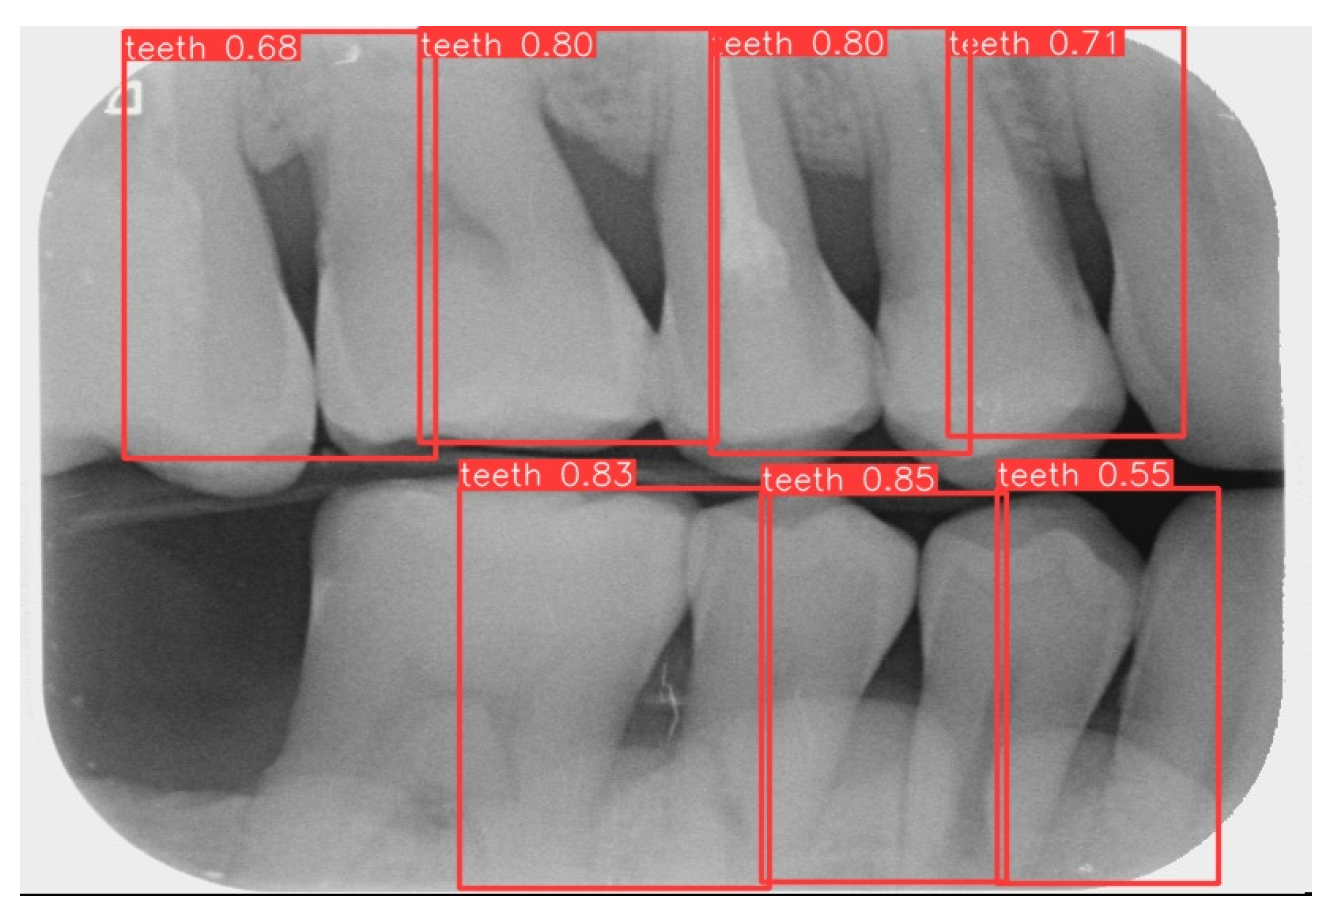

3.1. Image Segmentation

This study uses YOLOv8 to detect the gingiva between each tooth and record its coordinates. The parameters are listed in Table 6. The final target detection results of this study are shown in Figure 8. The comparison between the YOLO detection model and other studies is presented in Table 7. The image shows that the gum features are completely preserved, providing a reliable basis for CNN.

Figure 2. Image annotation and segmentation. (a) Image Annotation Diagram. (b) The tooth segmentation result.

Figure 8. YOLOv8 detection result.